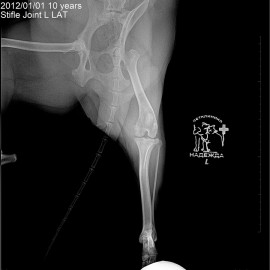

Наш пациент собака по кличке Буся.

Обратились с жалобами на хромоту на левую заднюю лапу.

Были проведены исследования, после которых был поставлен диагноз: разрыв передней крестообразной связки левого коленного сустава. Была проведена операция: TPLO.

Снимки 3-4 после операции.